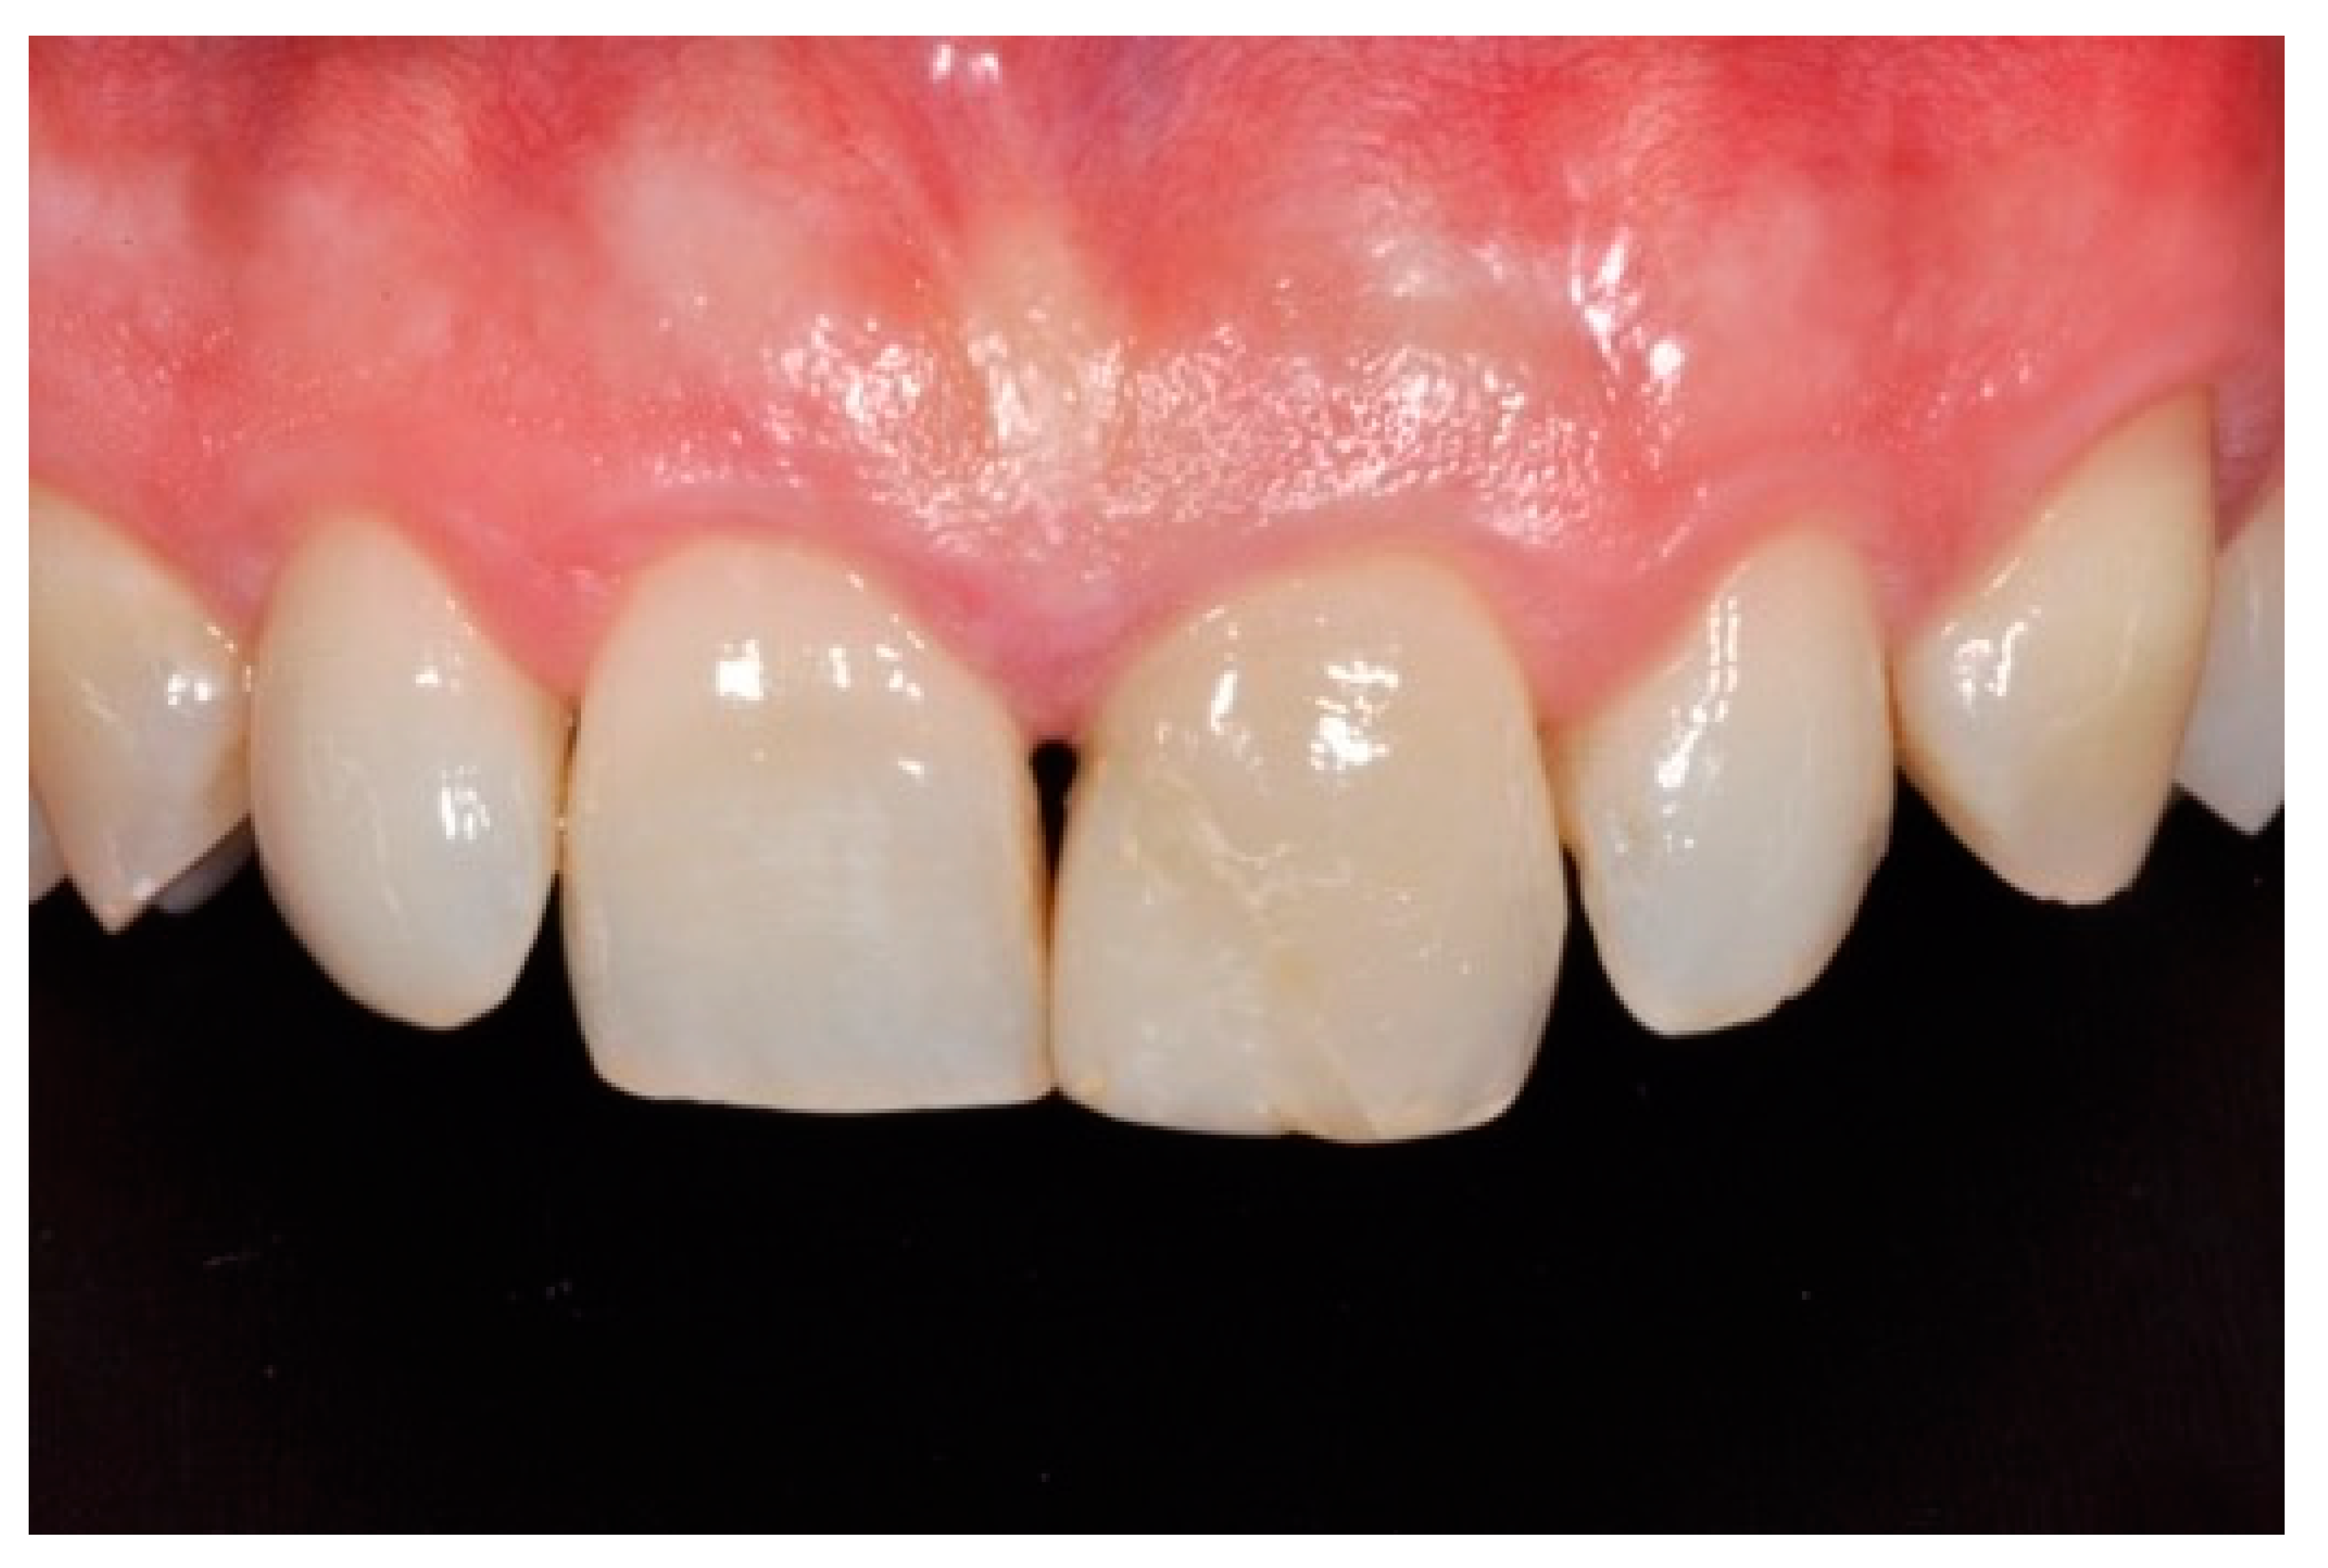

A healthy 10-year boy presented to the dental office after traumatic accident during sport activity. Upper central incisor presented horizontal fracture with no pulp exposure (Figure 1 and Figure 2). Tooth fragment was not retrieved after the traumatic accident. The tooth responded positively to pulp tests (cold and electrical). In order to manage sensitivity and protect the tooth before the restoration appointment, after rubber dam placement, a universal adhesive (Clearfil Universal Bond Quick, Kuraray Noritake Dental, Tokyo, Japan) was applied in self-etch mode followed by a little layer (approximatively 0.5 mm) of flowable composite (Clearfil Majesty ES Flow, A2, Kuraray Noritake Dental, Tokyo, Japan). A silicone impression (Imprint, 3M ESPE, St. Paul, MN, USA) was therefore taken in order to develop a wax-up (Figure 3) and a palatal silicone index (Elite HD+, Zhermack, Badia Polesine, Italy).

Figure 1.

Initial clinical situation. Reprinted from Restauri diretti nei settori anteriori, G. Paolone, S. Scolavino, © 2021, with permission from Quintessence Publishing Italy.